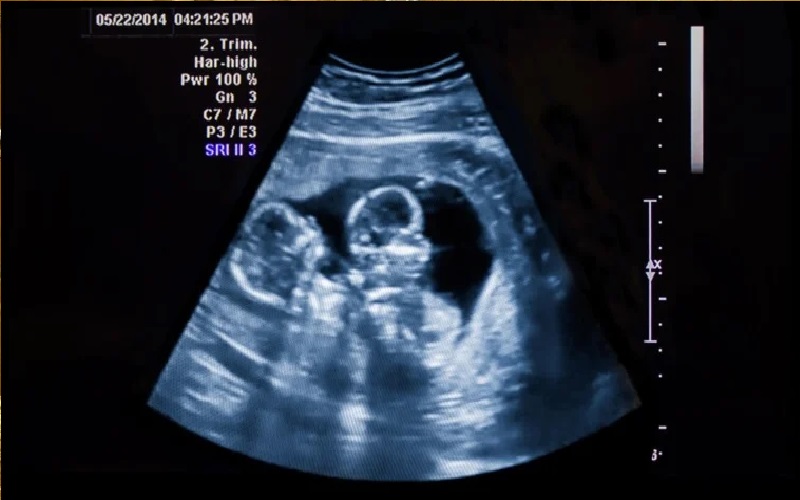

توتر الحامل يؤثر على نمو قلب الجنين

نيسان ـ يمكن أن يؤدي التعرض لمستويات عالية من هرمون التوتر الأساسي في الجسم - الكورتيزول - لدى الأجنة الخدّج إلى خلل في النمو الطبيعي للقلب، ما قد يزيد من خطر الإصابة بأمراض القلب والأوعية الدموية في مراحل لاحقة من الحياة.

هذا ما توصلت إليه دراسة جديدة أجرتها جامعة ساوث أستراليا، أظهرت أن ارتفاع مستويات الكورتيزول لدى الجنين يغيّر بشكل كبير الجزيئات التي تتحكم في النمو السليم للقلب.